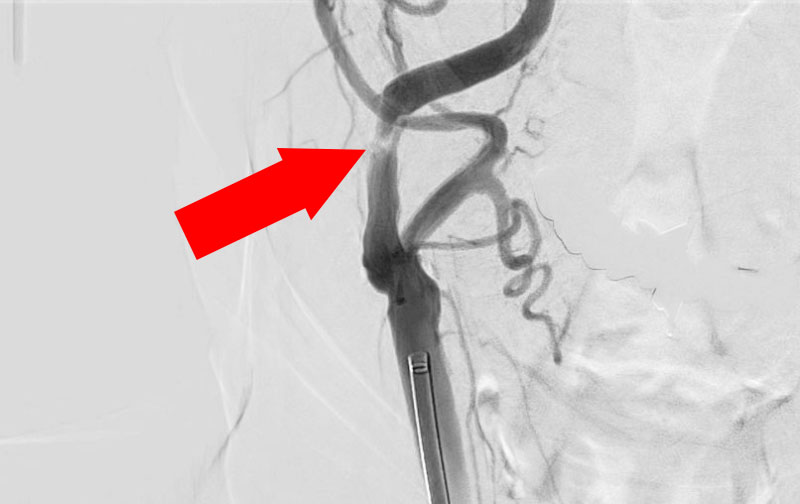

1210

'22年3月22日

右頚部内頚動脈狭窄症

80代

大阪府の病院